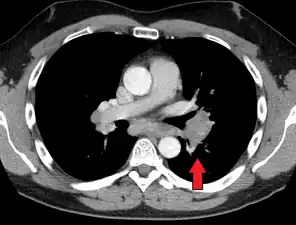

Chest radiograph changes are divided into four stages:[105]

- bihilar lymphadenopathy

- bihilar lymphadenopathy and reticulonodular infiltrates

- bilateral pulmonary infiltrates

- fibrocystic sarcoidosis typically with upward hilar retraction, cystic and bullous changes

Although people with stage 1 radiographs tend to have the acute or subacute, reversible form of the disease, those with stages 2 and 3 often have the chronic, progressive disease; these patterns do not represent consecutive "stages" of sarcoidosis. Thus, except for epidemiologic purposes, this categorization is mostly of historic interest.[28]

Hilar adenopathy especially on the person's left (AP CXR)

Hilar adenopathy especially on the person's left (lateral CXR)

Hilar adenopathy especially on the person's left (coronal CT)

Hilar adenopathy especially on the person's left (transverse CT)